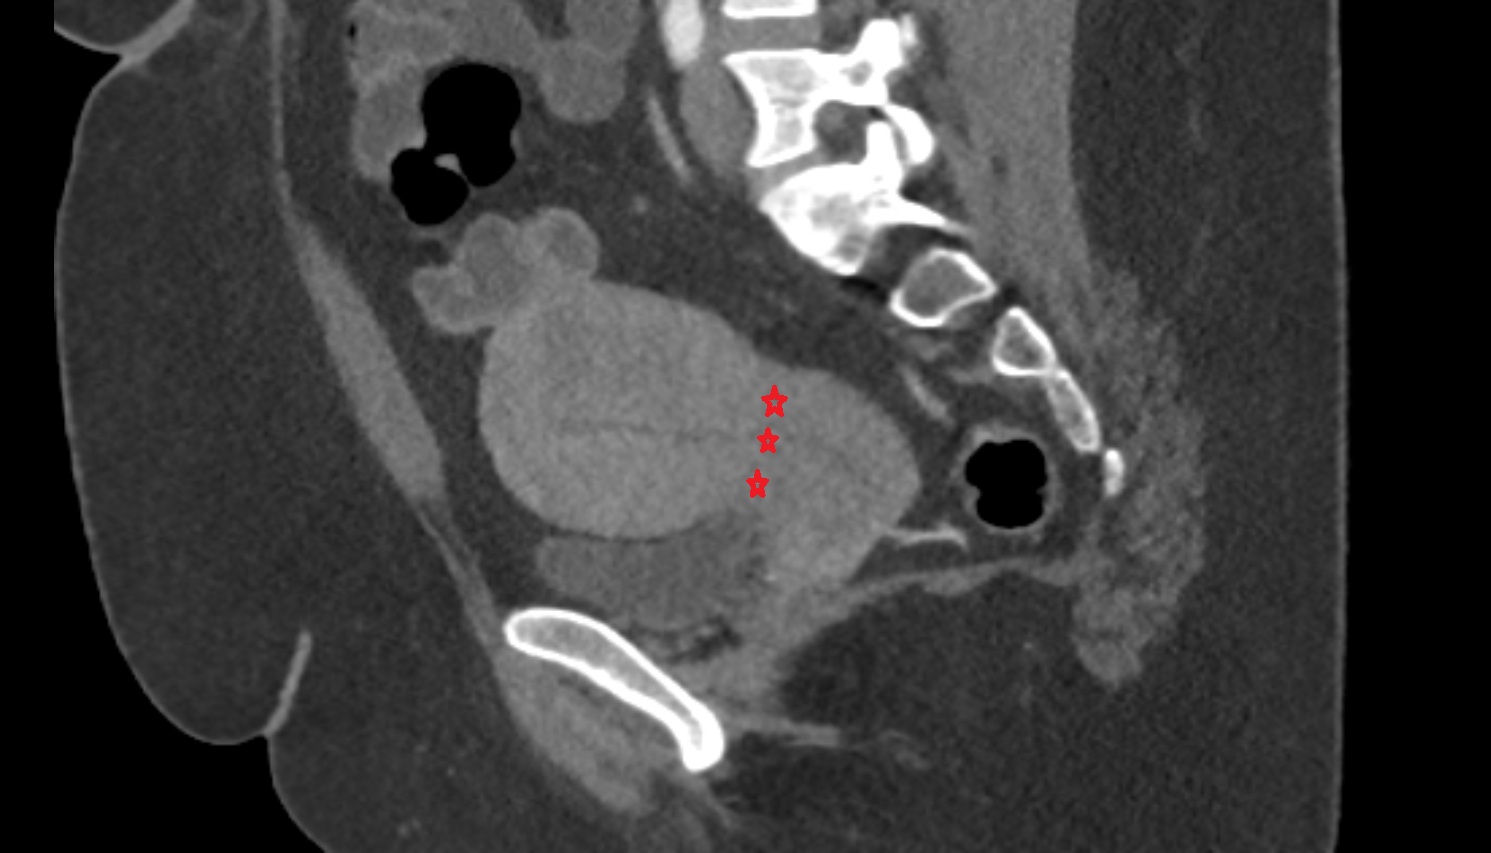

- Urinary bladder

- Uterus

- Body of uterus

- Fundus of uterus

- Cervix of uterus

- Isthmus of uterus

- Rectum

- Vesicouterine pouch

- Rectouterine pouch (pouch of Douglas)